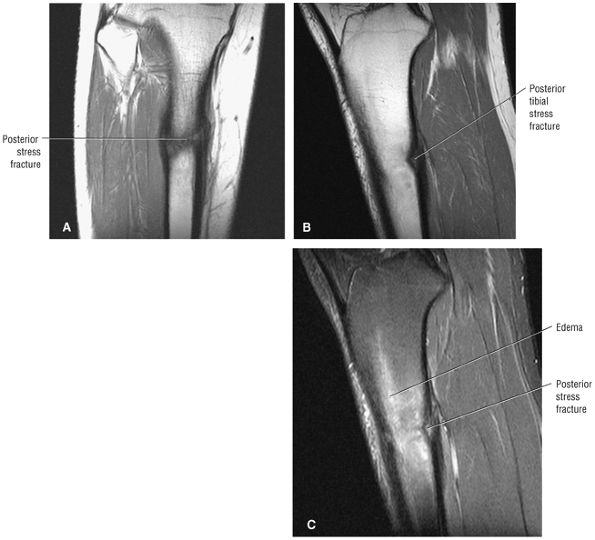

Stage I: Subchondral trabecular compression. Radiograph results are negative, bone scans are posi-tive, and marrow edema is seen on MR imaging (Fig. 5.95).

-